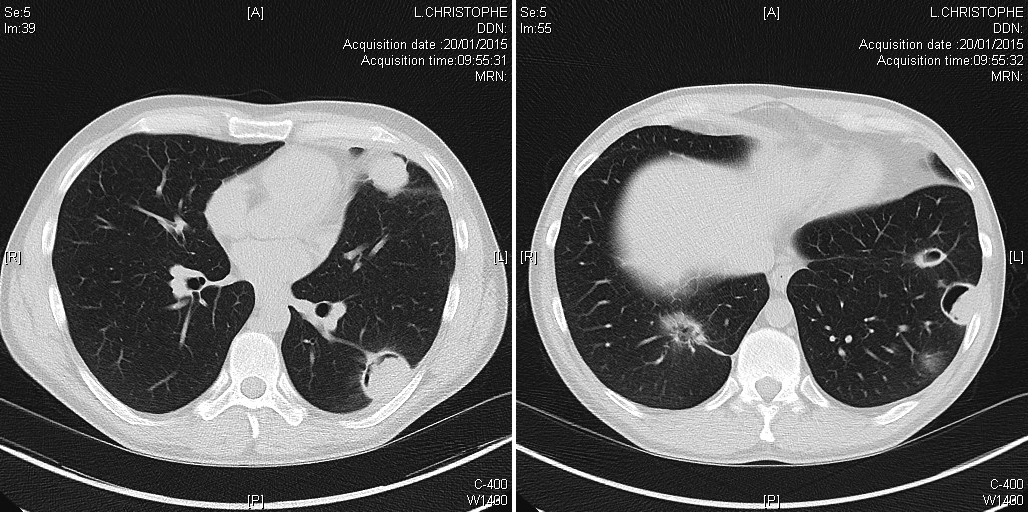

Nodules plumonaires excavés dans le cadre d'une granulomatose avec polyangéite